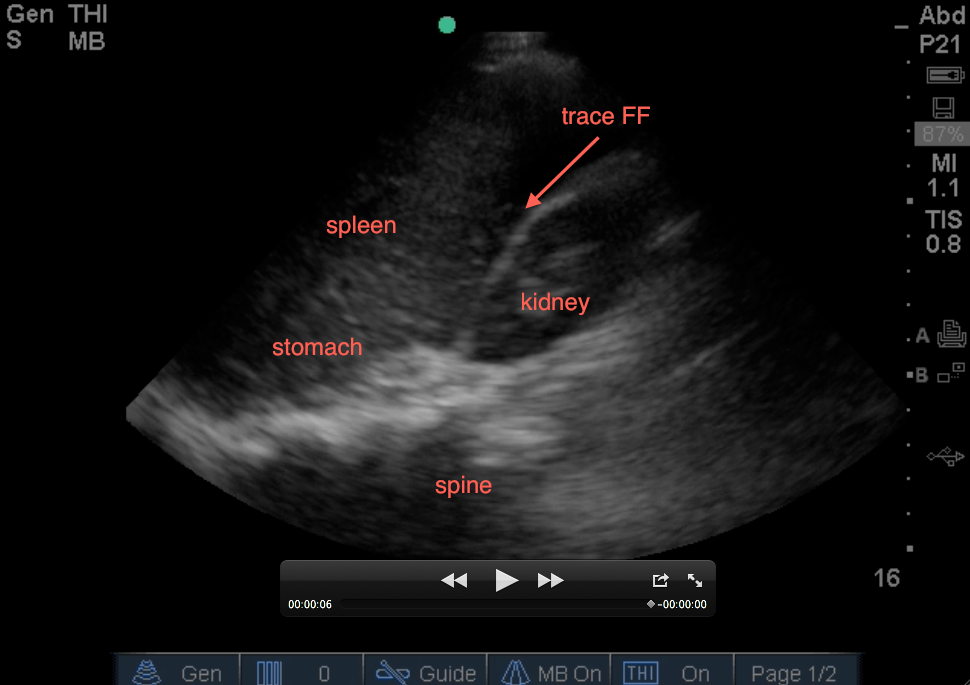

3. Evaluate between the spleen and the entire superior pole of the kidney. Slowly fan anterior to posterior to visualize the entire superior pole of kidney – you should fan to the extent that the kidney goes completely out of view, comes back into view, then goes back out of view. This area will have free fluid in addition to the other regions of the LUQ. It’s the last area for free fluid to collect.

4. Evaluate between the left edge of the spleen and the entire inferior pole of the kidney. This will also evaluate the left paracolic gutter. You will need to travel down one rib space in order to evaluate this region. The below video shows trace free fluid at the very left paracolic gutter with complete fanning (it also shows hydronephrosis)